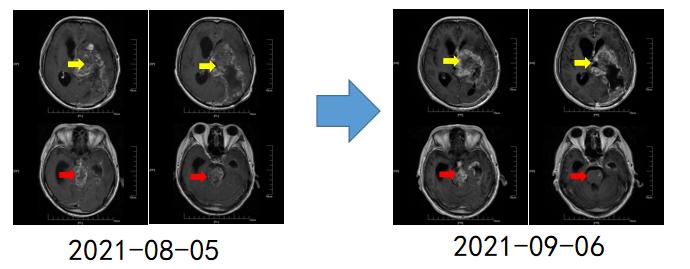

患者甲,因“癫痫大发作1次”于2018年10月6日入住上海某医院,同年10月23日在上海行手术切除治疗,术后病理为少突胶质细胞瘤(WHO III级)。术后进行规范化治疗,今年6月因右侧肢体肌力下降,复查MRI提示肿瘤复发或放射性坏死可能(下图A、B)。今年6月17日,在我院行右侧额叶异常信号切除,术后病理提示肿瘤坏死可能,患者为求下一步诊疗方案,在我院MDT门诊就诊。经胶质瘤MDT团队联合诊疗后诊断考虑为放射性坏死,予以贝伐单抗200mg q3w进行治疗,同时进行康复功能锻炼,今年9月复查MRI提示异常信号缩小(图1C,D),患者右侧肢体肌力恢复至IV-级,可在辅助物帮助下进行站立,目前治疗仍在持续中。

【图1.典型病例一:2021-09复查MRI(C,D)提示异常信号较前(A,B)明显缩小】